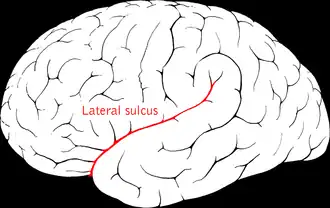

Lateral sulcus

The lateral sulcus (or lateral fissure, also called Sylvian fissure, after Franciscus Sylvius) is the most prominent sulcus of each cerebral hemisphere in the human brain. The lateral sulcus is a deep fissure in each hemisphere that separates the frontal and parietal lobes from the temporal lobe. The insular cortex lies deep within the lateral sulcus.

The lateral sulcus divides both the frontal lobe and parietal lobe above from the temporal lobe below. It is in both hemispheres of the brain. The lateral sulcus is one of the earliest-developing sulci of the human brain, appearing around the fourteenth week of gestational age.[1]

The lateral sulcus has a number of side branches. Two of the most prominent and most regularly found are the ascending (also called vertical) ramus and the horizontal ramus of the lateral fissure, which subdivide the inferior frontal gyrus. The lateral sulcus also contains the transverse temporal gyri, which are part of the primary and below the surface auditory cortex.

Due to a phenomenon called the Yakovlevian torque, the lateral sulcus is often longer and less curved on the left hemisphere than on the right.

Lateral sulcus shown in red (animation)

Lateral sulcus shown in red (animation)